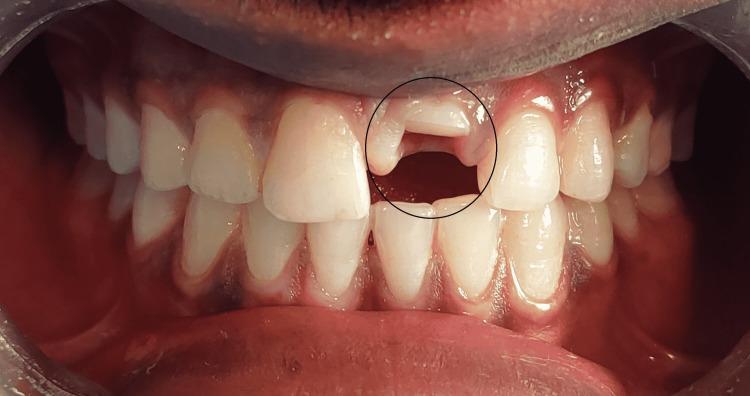

Among the various types of dental trauma, crown-root fractures are one of the most challenging to treat and require a multidisciplinary approach. This paper reports a case of a complicated crown-root fracture of maxillary left central incisor with esthetic, functional complications. An 18-year-old male patient presented to the department immediately after suffering trauma with a complicated crown-root fracture on tooth 21. As per the treatment, the patient had undergone endodontic therapy followed by flap reflection. Post flap reflection, a glass fiber post was luted, and the fractured fragment was reattached. By this approach, in the same appointment, the cervical margin can be exposed with appropriate isolation followed by a reattachment procedure. Reattaching the fragment is a viable option as it can be done immediately, provides better esthetics, restores function, and is less complicated than the conventional approach. A good prognosis is dependent on patient cooperation with the understanding of the treatment limitations. The article discusses a successful case of complicated crown-root fracture treated with the reattachment of a tooth fragment. Eighteen months of clinical and radiographic evaluation revealed that the clinical protocol was effective, as the tooth was functional, asymptomatic, and esthetic.

在各类牙外伤中,冠根折是治疗难度最大的情况之一,需要多学科联合治疗。本文报告一例上颌左侧中切牙复杂冠根折伴美观和功能并发症的病例。一名18岁男性患者在牙外伤后立即就诊,其21号牙发生复杂冠根折。按照治疗方案,患者先接受了根管治疗,随后进行了翻瓣术。翻瓣术后,粘结了玻璃纤维桩,并重新附着了骨折碎片。通过这种方法,在同一次就诊中,可以在适当隔离的情况下暴露颈部边缘,然后进行重新附着操作。重新附着碎片是一种可行的选择,因为它可以立即进行,美观效果更好,能恢复功能,且比传统方法更简单。良好的预后取决于患者对治疗局限性的理解并配合治疗。本文讨论了一例通过重新附着牙碎片成功治疗复杂冠根折的病例。18个月的临床和影像学评估显示,该临床方案是有效的,因为患牙功能正常、无症状且美观。